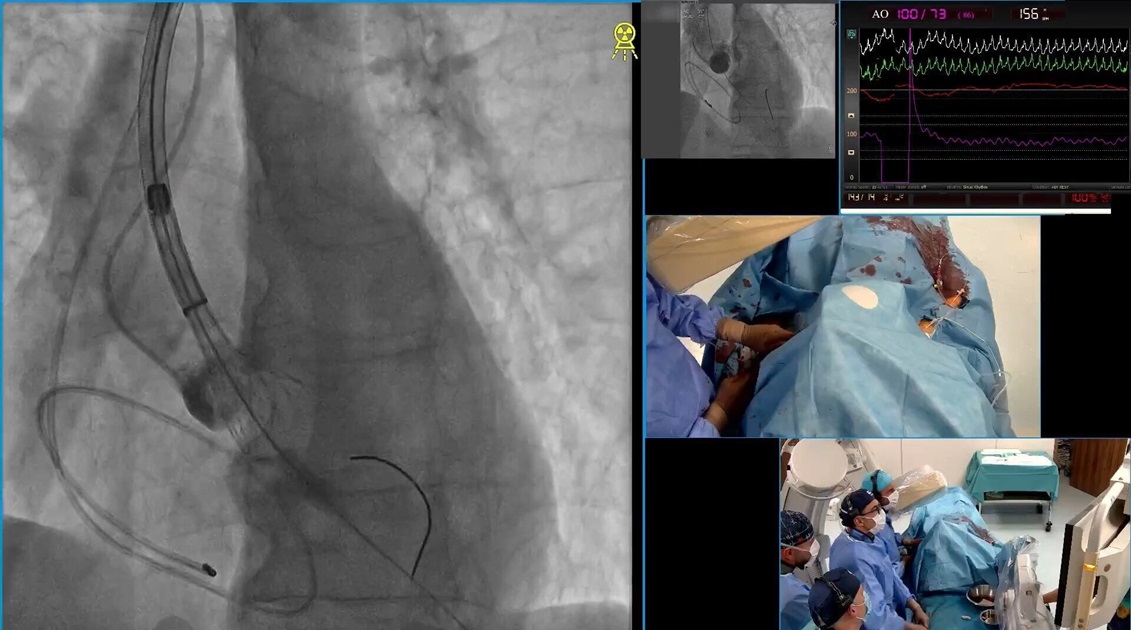

След обсъждане на кардиологичен колегиум дамата бива преценена за имплантация на транскатетърна биологична аортна клапа – TAVI с алтернативен достъп през лявата подключична артерия.

Екипът на проф. Иво Петров и доц. Станков осъществява интервенцията изцяло ендоваскуларно през ръката. Процедурата е комплексна и сложна, поради което решихме да я споделим с вас ТУК.